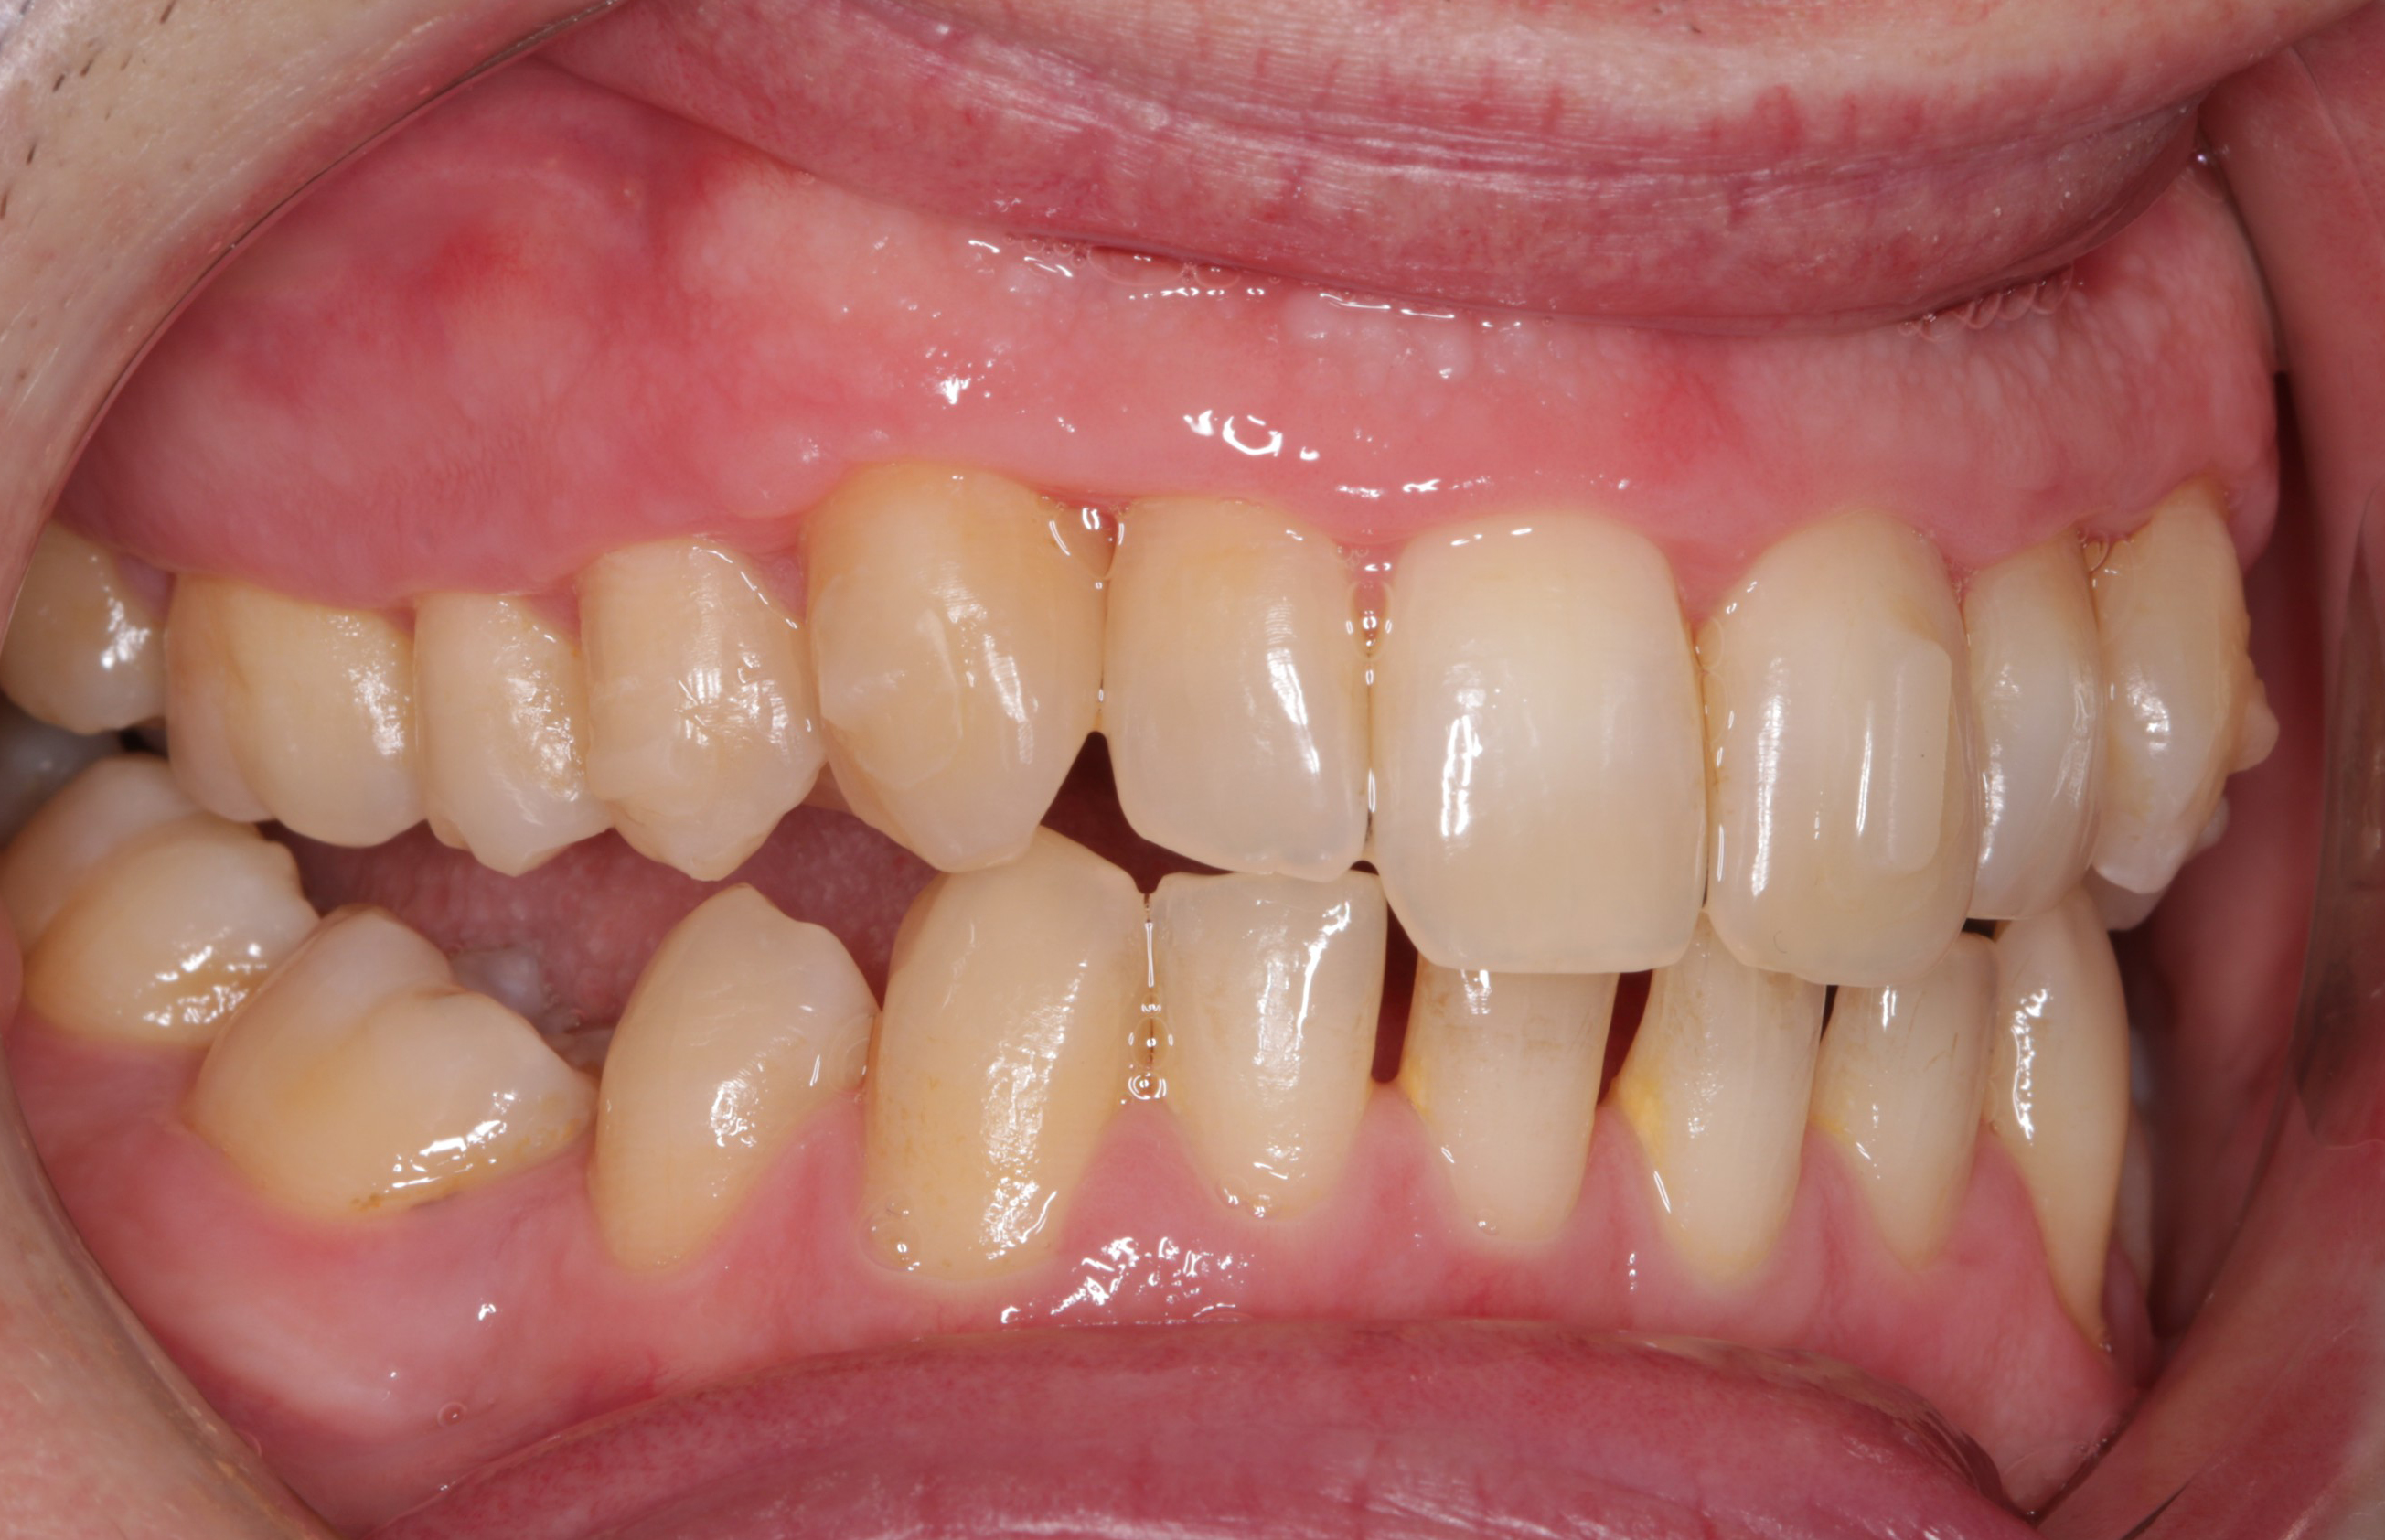

Actual before and after of Invisalign treatment needing refinement Aligner Refinement It is not a bad thing if your dentist suggests refinements, it just means that they are making sure you get the most out of your treatment. When the teeth are not being aligned properly, or the gaps between the teeth are not being closed as planned, it may be necessary to make adjustments. Invisalign refinements are additional sets of. Aligner Refinement.